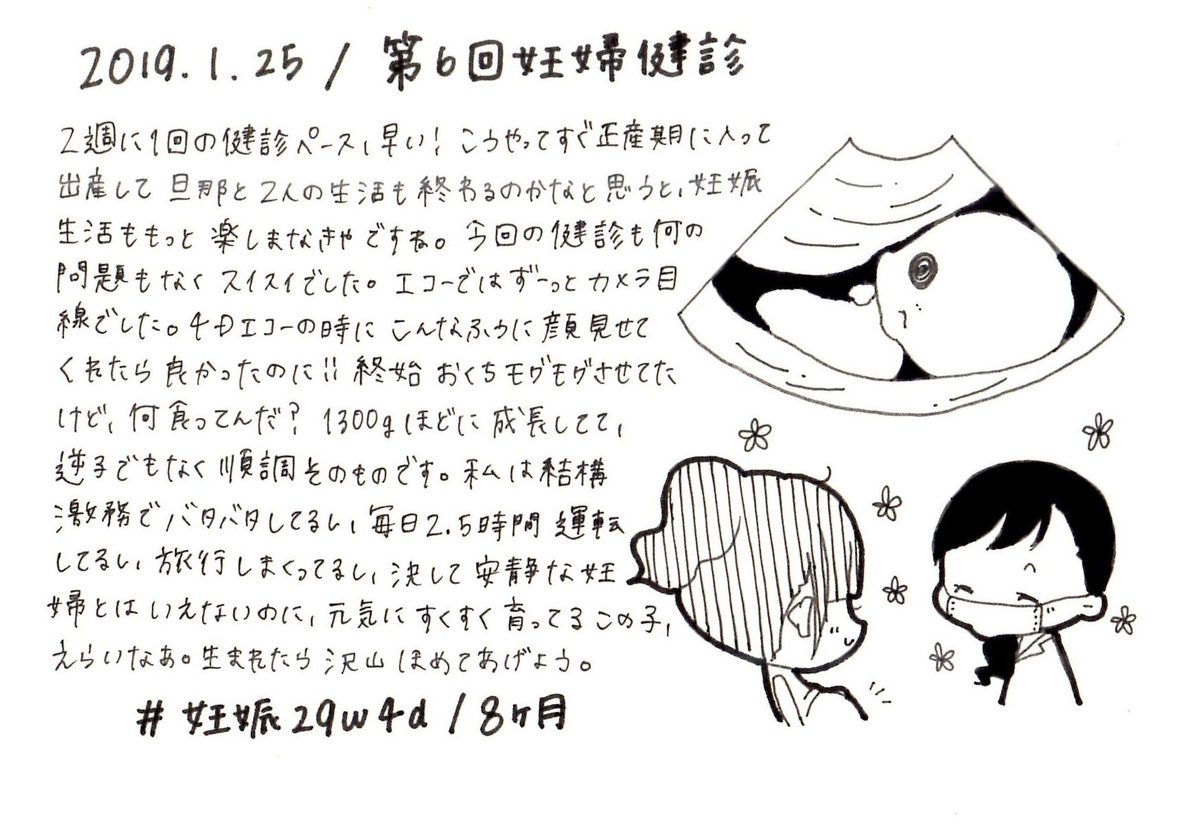

2019.1.25 すくすく成長してくれてるのが本当にありがたい。エコーでももう完全に人間が写ってて可愛いです。 エコーとお腹の写真載せます、閲覧注意! #育児漫画 #育児日記 #妊娠 #妊娠後期 #妊娠8ヶ月 #妊婦健診 #エコー #ママ垢さんと繋がりたい #オリジナル漫画 #絵描きさんと繫がりたい pic.twitter.com/kMN6lg0NRS

2019-09-01 11:41:52 拡大

拡大

拡大

拡大